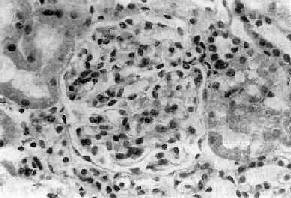

病变为弥漫性。镜下可见大部分肾小球内有新月体形成。新月体主要由肾小球上皮细胞增生和渗出的单核细胞组成。肾小球上皮细胞主要是壁层上皮细胞增生显著,堆积成层,在肾球囊内毛细血管丛周围呈新月形或环状,故称为新月体或环状体(图12-12)。新月体形成很快,可在发病后数日内形成。增生的上皮细胞间可见红细胞、中性粒细胞和纤维素性渗出物。有时可见球丛毛细血管发生纤维素样坏死和出血。肾球囊内的纤维蛋白可刺激上皮细胞增生,是促使新月体形成的原因。系膜和内皮细胞也增生,但一般程度较轻。早期新月体主要由增生的上皮细胞和单核细胞组成,称为细胞性新月体。新月体内增生的上皮细胞之间逐渐出现新生的纤维细胞,以后纤维组织逐渐增多形成纤维-细胞性新月体。最后新月体内的细胞和渗出物完全由纤维组织替代,成为纤维性新月体。

图12-12 新月体性肾小球肾炎

肾球囊壁层上皮细胞增生,其间有单核巨噬细胞浸润形成新月体,肾球囊腔被阻塞